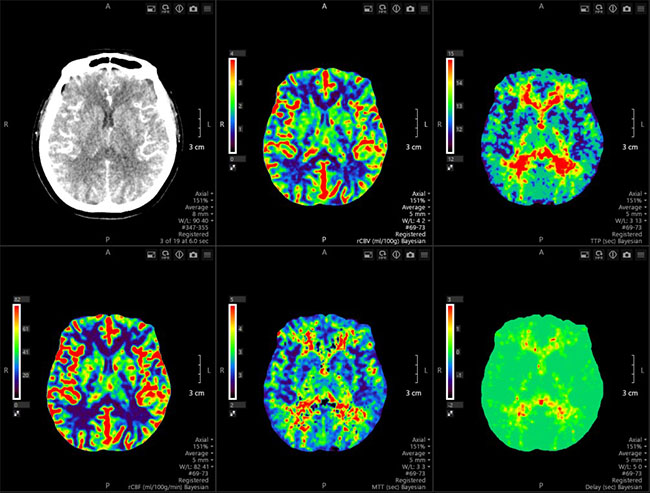

- 腦部血流灌注檢查:常用於腦梗塞患者,來評估腦部組織是否有缺血或梗塞壞死的情況與範圍。